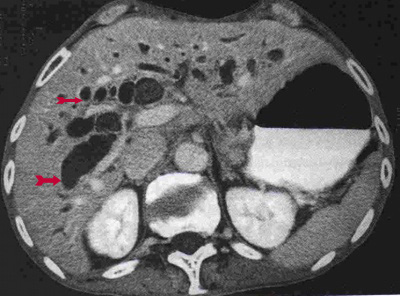

ב- CT המבוצע לחולים אלה במסגרת בירור כאבי בטן אפשר לראות הרחבה של דרכי המרה (תצלום 33.8) וכן אבנים בדרכי המרה (תצלום 34.8 ) למרות שאין זו בדיקת הבחירה לאבנים בדרכי המרה.